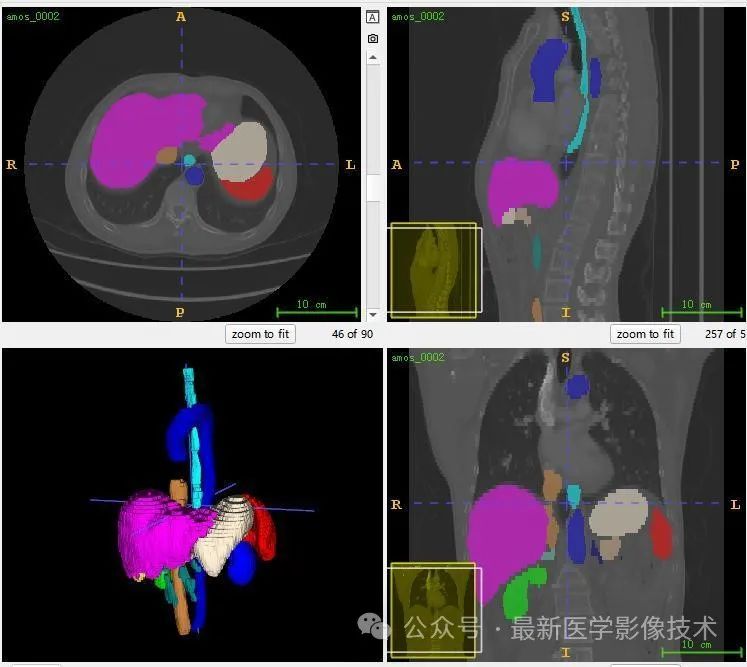

12、验证集分割结果

左图是金标准结果,右图是预测结果。